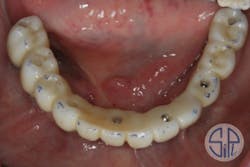

The fractured zirconia restoration was sectioned into two pieces, sandblasted, and then reseated as separate pieces. A new impression coping was placed on transmucosal abutment No. 27 (figure 7). All three pieces were luted together with resin as a new abutment level "pickup" impression (figure 8).

Figure 7: New impression coping placed on transucosal abutment No. 27

Figure 8: New abutment level "pickup" impression, with all three pieces luted together

The lab poured up a new model and milled a new zirconia restoration, which was delivered (whole this time!) with ease (figure 9).